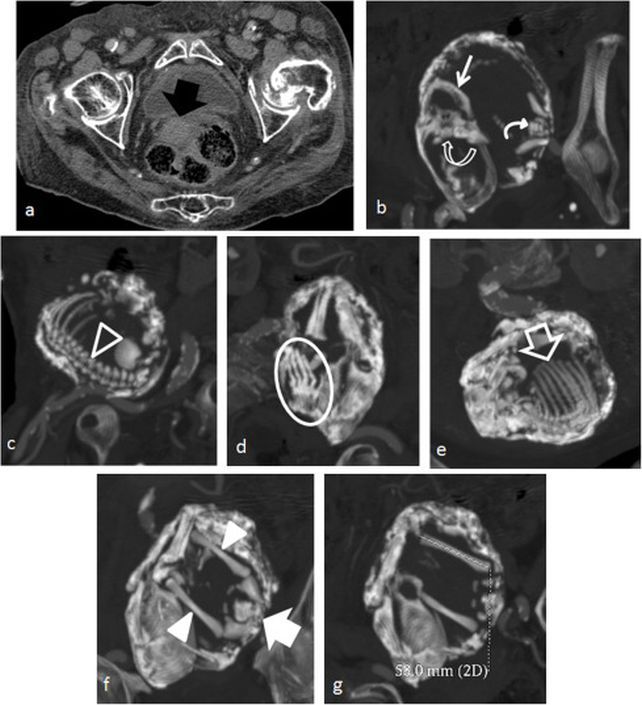

При абдомінальній вагітності організм здатний захистити себе, коли плід гине, перетворюючись на "камінь". Насправді ж це не камінь, а метал. Тіло матері просочує плід металевим мінералом кальцієм, основним компонентом кісток, у процесі, відомому як кальцифікація. Це безпечно відокремлює плід від власного організму матері, захищаючи його від сепсису.